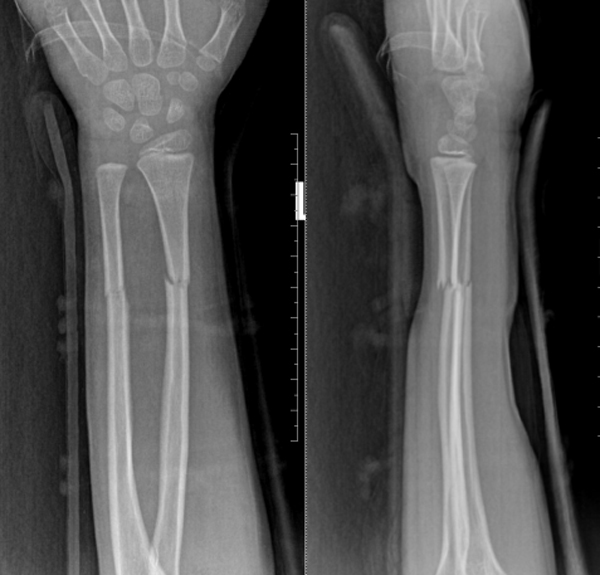

复位后X光复查